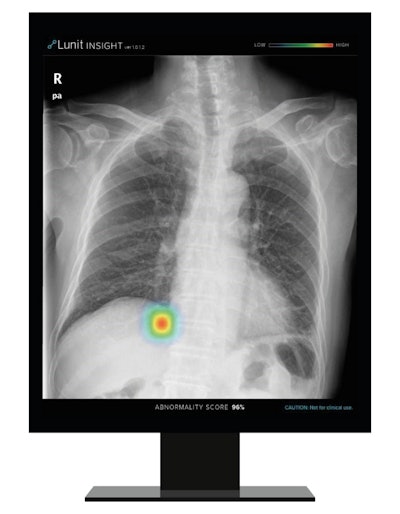

Artificial intelligence (AI) software developer Lunit is making its chest imaging software available on x-ray systems from Philips Healthcare through a new partnership announced at the virtual ECR 2021.

South Korea-based Lunit noted that its Insight CXR AI software is helpful for real-time detection of 10 common findings on chest x-rays and enables triage of cases to focus on those with likely abnormalities. The company said that the software's accuracy rate is high, ranging from 97% to 99%.